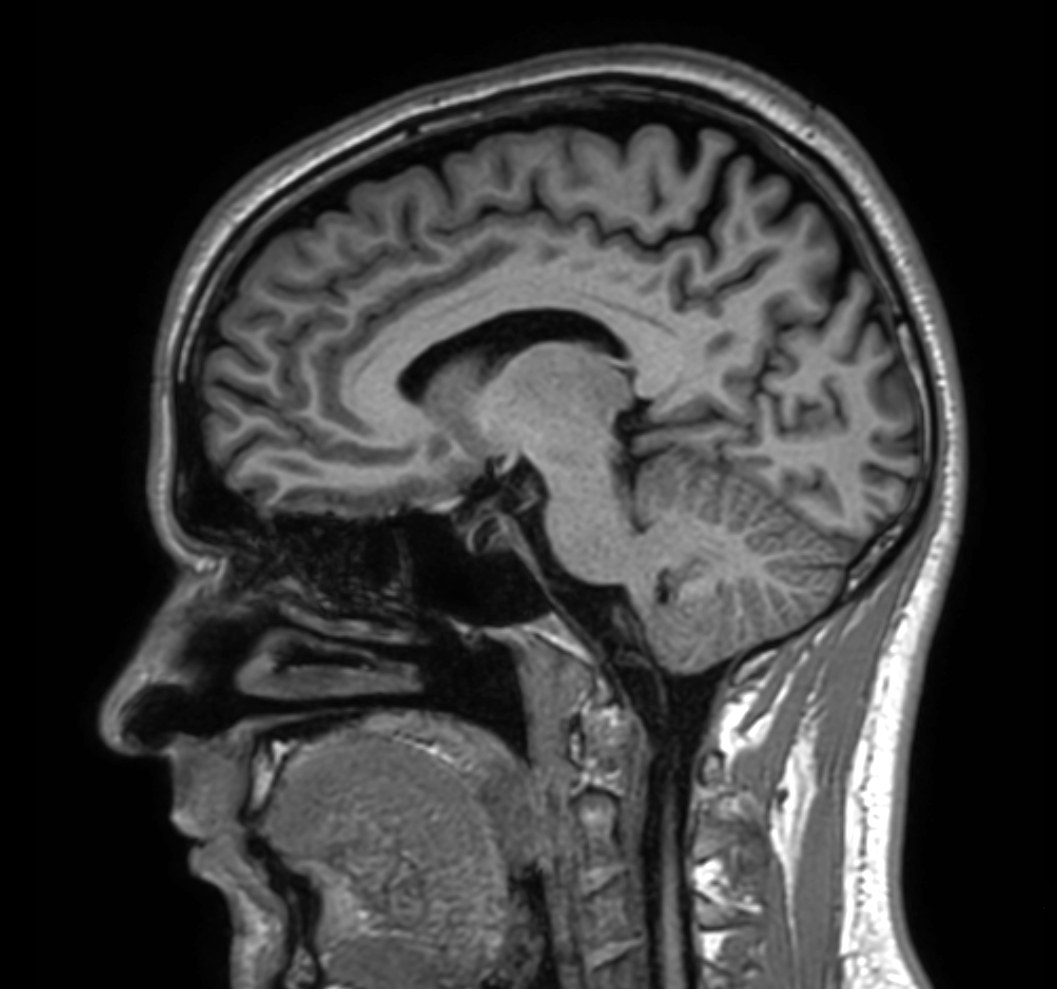

Sagittal 3D T1w TFE with ComforTone